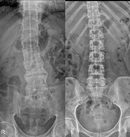

"허리가 삐뚤어졌어요"…'이 질환' 방치시 보행장애 온다

류난영기자2025.10.29 01:01:00